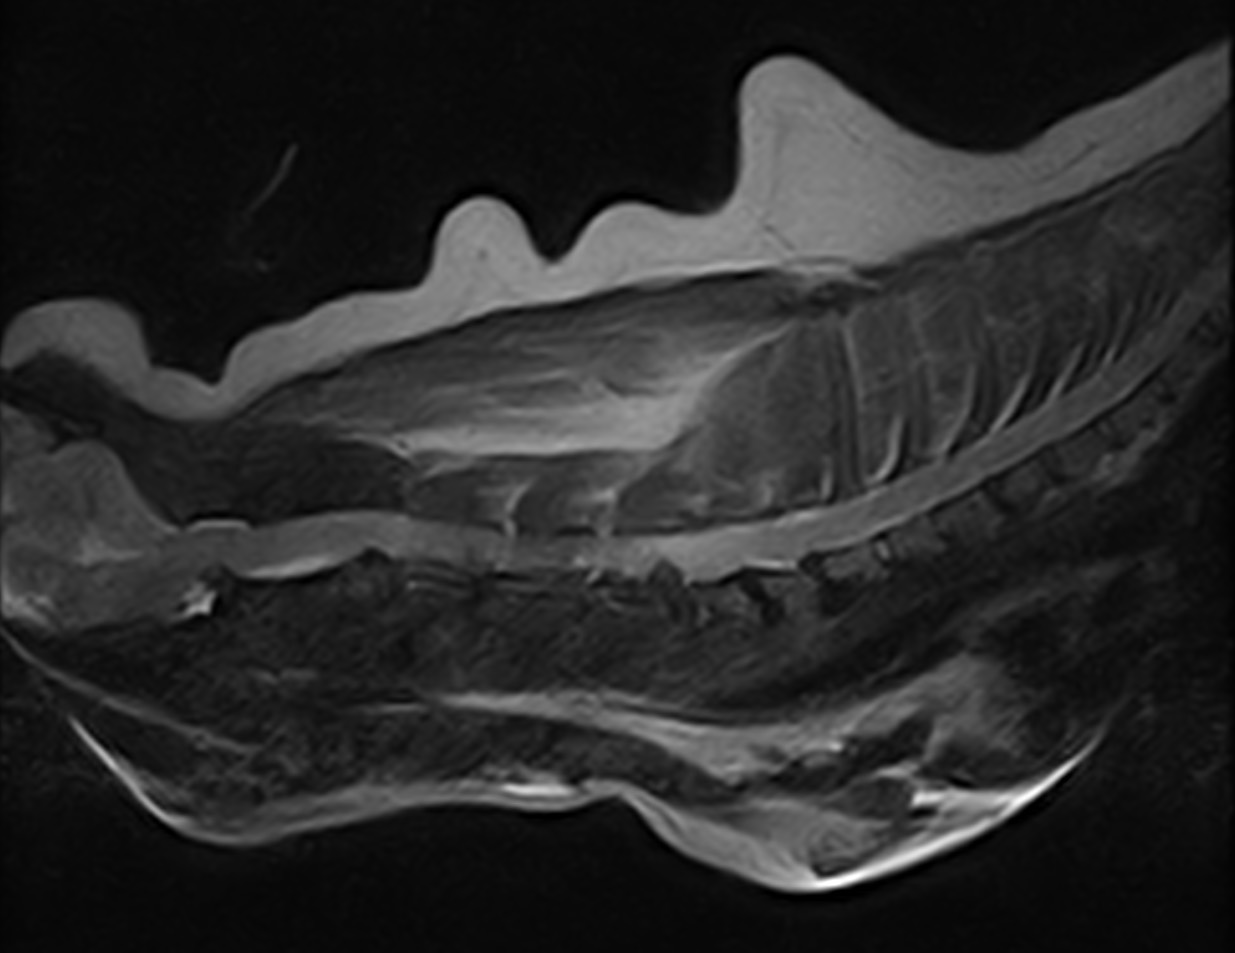

高齢のミニピンさんが突然、頸を痛がり四肢不全麻痺になったとのことで主治医より検査と治療目的で来院しました。MRIではC5~C6に圧迫が確認されました。Ventral Slotでアプローチし、椎間板を除去しました。術後は鍼治療も併用し、治癒を促進を期待します。

高齢のミニピンさんが突然、頸を痛がり四肢不全麻痺になったとのことで主治医より検査と治療目的で来院しました。MRIではC5~C6に圧迫が確認されました。Ventral Slotでアプローチし、椎間板を除去しました。術後は鍼治療も併用し、治癒を促進を期待します。